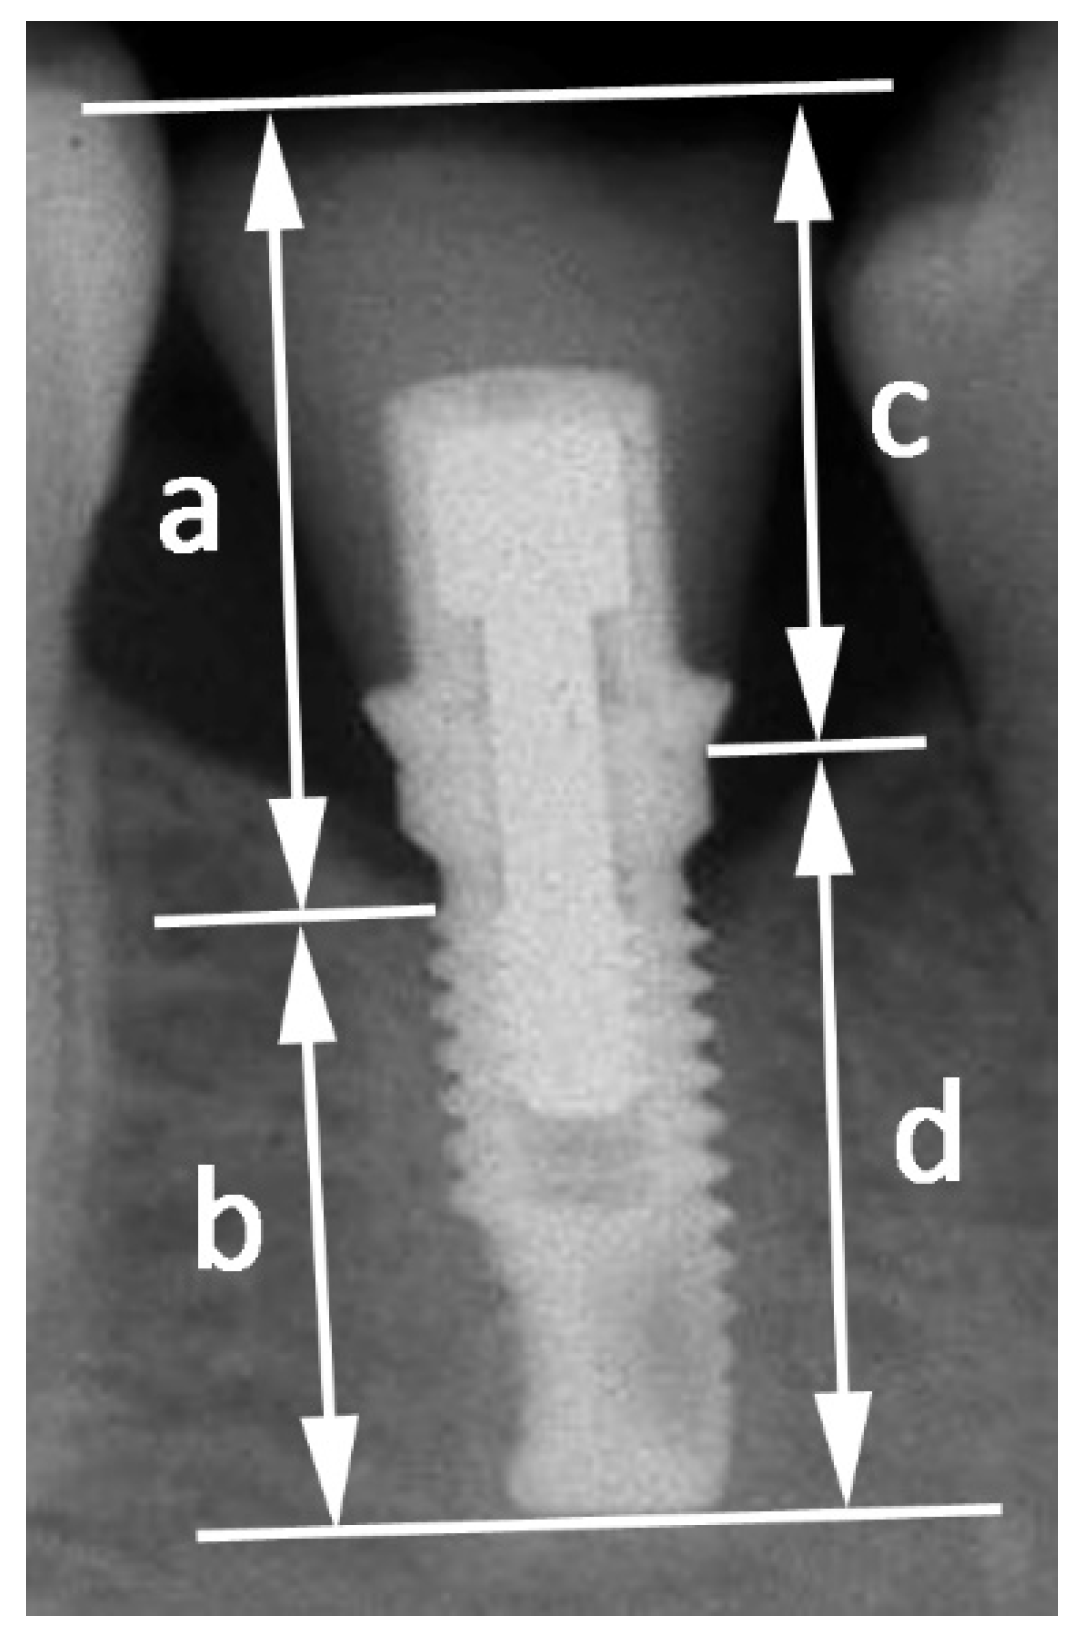

(PDF) Importance of crown to root and crown to implant ratios Crown To Root Ratio For Abutment however, controversy persists as to its impact on diagnosis and treatment planning. Clinical procedures directly affect the crr. This article critically reviews the available. The subject of this in vitro. The primary objective in evaluating clinical criteria for abutments and periodontally. Crown To Root Ratio For Abutment.

Crowntoimplant ratios of single tooth implantsupported restorations Crown To Root Ratio For Abutment The primary objective in evaluating clinical criteria for abutments and periodontally. Clinical procedures directly affect the crr. however, controversy persists as to its impact on diagnosis and treatment planning. The subject of this in vitro. This article critically reviews the available. Crown To Root Ratio For Abutment.

JCM Free FullText Influence of CrownImplant Ratio and Implant Crown To Root Ratio For Abutment Clinical procedures directly affect the crr. The subject of this in vitro. however, controversy persists as to its impact on diagnosis and treatment planning. The primary objective in evaluating clinical criteria for abutments and periodontally. This article critically reviews the available. Crown To Root Ratio For Abutment.